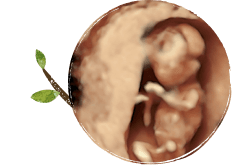

婦人科、妊婦検診、出生前検査